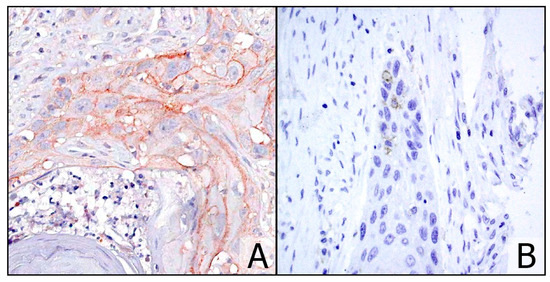

2.3. Immunohistochemistry